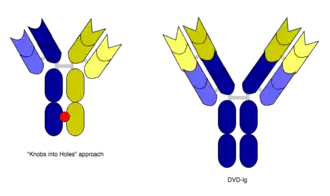

The original concept of BsAbs was proposed by Nisonoff and his collaborators in the 1960s, including the first idea of antibody architecture and other findings.[4][5] In 1975, the problem of producing pure antibodies was solved by the creation of hybridoma technology, and the new era of monoclonal antibodies (MoAbs) came.[6] In 1983, Milstein and Cuello created hybrid-hybridoma (quadroma) technology.[7] In 1988, the single-chain variable fragment (scFv) was invented by the Huston team to minimize the refolding problems, which contains the incorrect domain pairing or aggregation of two-chain species.[8] In 1996, the BsAbs became more developed when the knobs-into-holes technology emerged.[1][9]

However, the quadroma method relies on random chance to form usable BsAb, and can be inefficient. Another method for manufacturing IgG-like BsAb is called "knobs into holes," and relies on introducing a mutation for a large amino acid in the heavy chain from one mAb, and a mutation for a small amino acid in the other mAb's heavy chain. This allows the target heavy chains (and their corresponding light chains) to fit together better, and makes the production of BsAbs more reliable.[3][11]

In addition, in working with Ebolavirus vaccines, a study has shown that a DVD-Ig antibody can be used to prevent viral escape from the endosome. Ebolaviruses infect cells by receptor-mediated endocytosis. Researchers developed DVD-Igs where the outer variable regions bind to the surface glycoproteins of the viral coat and enter the cell with the virus. These outer regions are cleaved in the viral endosome, revealing the inner variable regions that then bind to both the virus and internal receptors in the endosome. Blocking the interaction between the virus and endosomal proteins prevents viral escape from the endosome and further infection.[24]